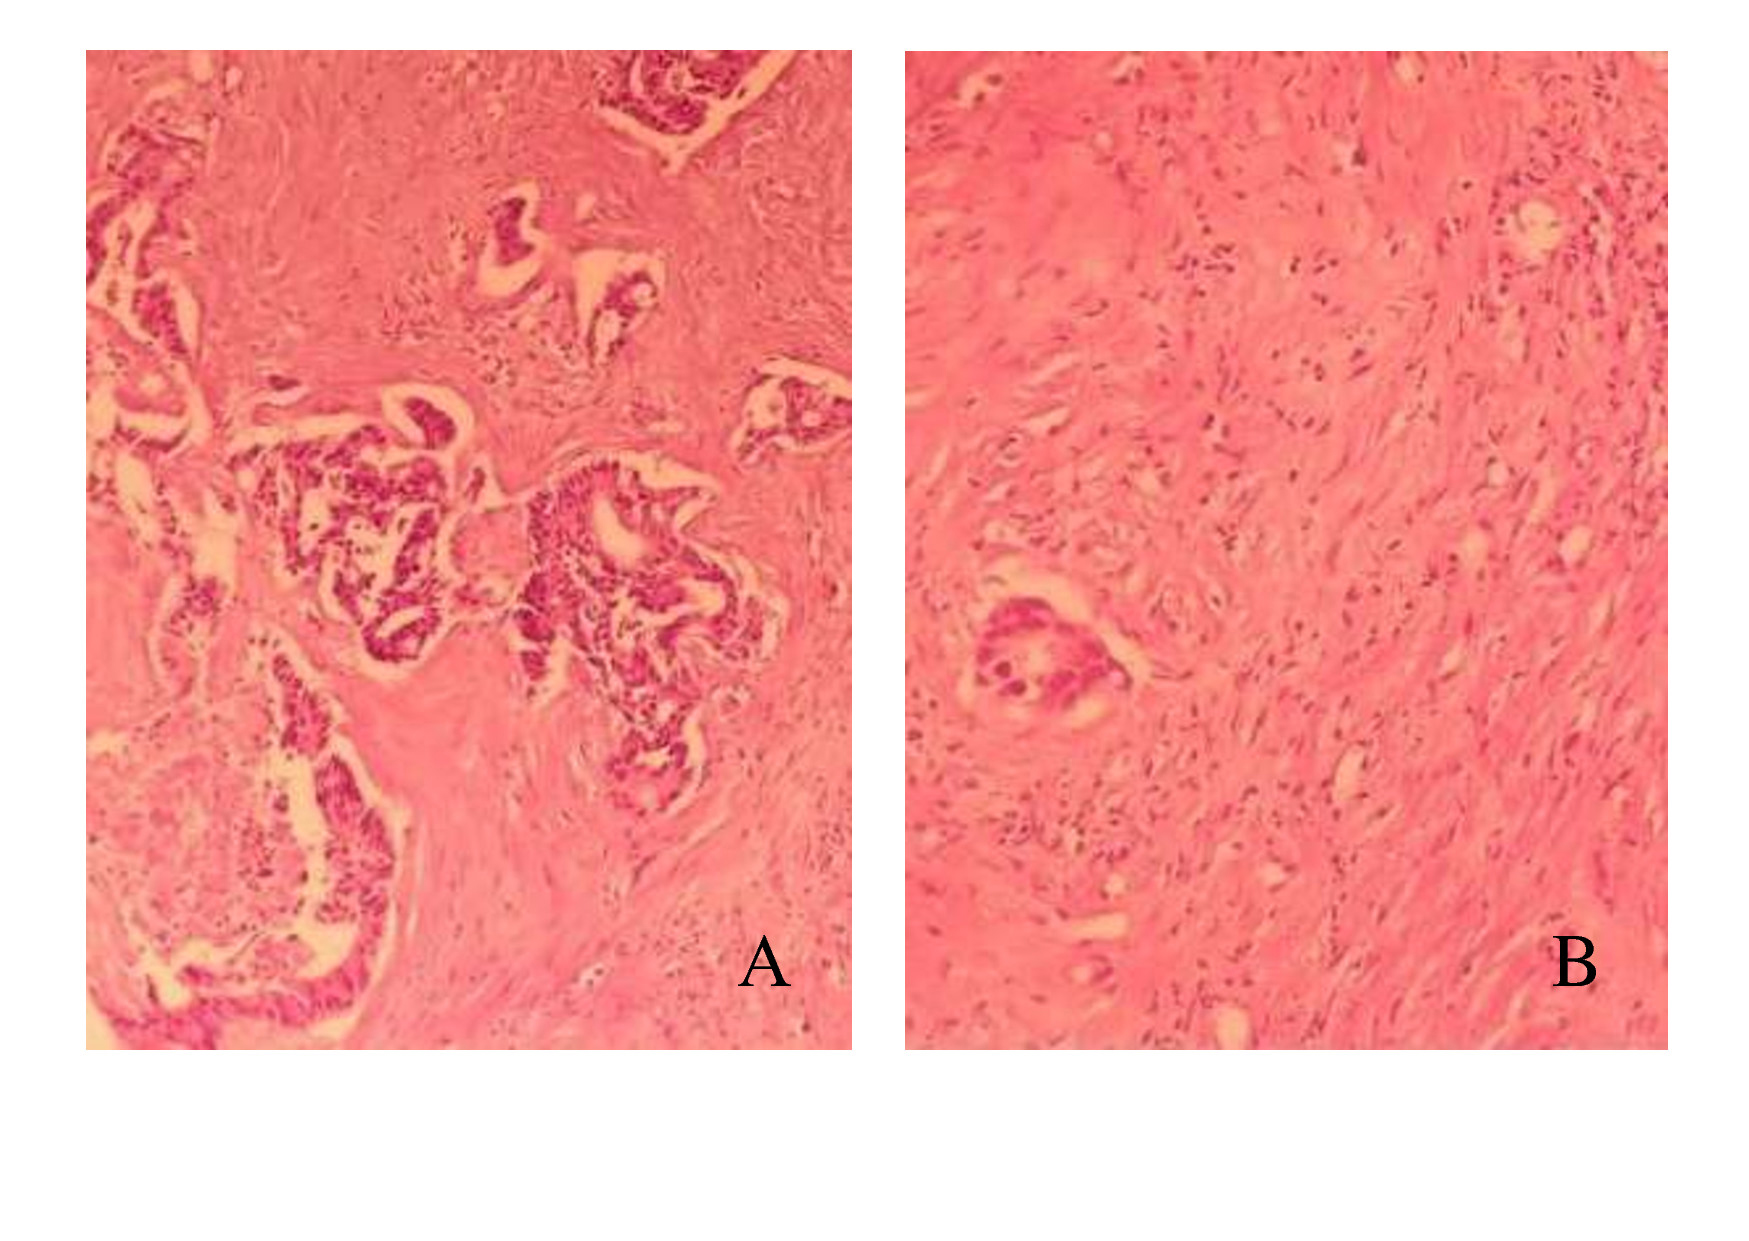

In the first group where resection operation was conducted in 7 days after the regional chemotherapy, the therapeutic pathomor-phism was observed in 13/15 patients. In 11/13 patients the 2nd degree of therapeutic pathomorphism was recorded that consisted in the existence of fibrosis fields and scarce inflammatory infiltration (Fig. 5) with the underlying preserved tumorous tissue.

Fig. 5. Metastasis of adenocarcinoma of intestinal type with the presence of fields of fibrosis (A) and inflammatory infiltration (B). The second degree of therapeutic pathomorphosis (color: hematoxylin and eosin, x 400)